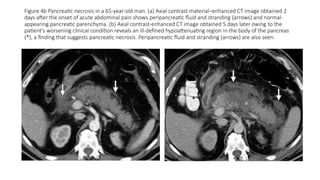

Figure 4b Pancreatic necrosis in a 65-year-old man. (a) Axial contrast material–enhanced CT image obtained 2

days after the onset of acute abdominal pain shows peripancreatic fluid and stranding (arrows) and normal-

appearing pancreatic parenchyma. (b) Axial contrast-enhanced CT image obtained 5 days later owing to the

patient’s worsening clinical condition reveals an ill-defined hypoattenuating region in the body of the pancreas

(*), a finding that suggests pancreatic necrosis. Peripancreatic fluid and stranding (arrows) are also seen.

Figure 4b Pancreaticnecrosis in a 65-year-old man. (a) Axial contrast material–enhanced CT image obtained 2 days after the onset of acute abdominal pain shows peripancreatic fluid and stranding (arrows) and normal- appearing pancreatic parenchyma. (b) Axial contrast-enhanced CT image obtained 5 days later owing to the patient’s worsening clinical condition reveals an ill-defined hypoattenuating region in the body of the pancreas (*), a finding that suggests pancreatic necrosis. Peripancreatic fluid and stranding (arrows) are also seen.